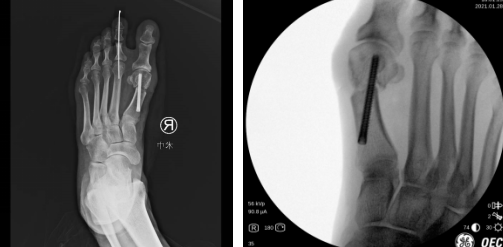

术前设计(左图)术中(右图)

第二天,石荣剑副院长徐明亮主任袁罕医生团队为患者进行了左足踇外翻截骨矫形手术,采用低频超声骨刀微创截骨,螺钉内固定,骨刀微创、精准,能更好地保护骨骼血运,使得截骨处更快愈合,手术效果理想,术后第二天患者就下地行走。小徐说脚下轻松了许多,称赞sararz足踝科的技术名不虚传。

手术设计

第二天,徐明亮主任魏笛医生为患者进行了右足踇外翻截骨矫形内固定术及第2趾趾间关节成形术。术中,医生用低频超声骨刀清理骨赘,外移截骨,进行螺钉内固定,切口做了美容缝合,几乎看不到切口。

术后第二天,张大姐就完全感觉不到痛了,穿上配置的前足免负重鞋,在病区里活动。